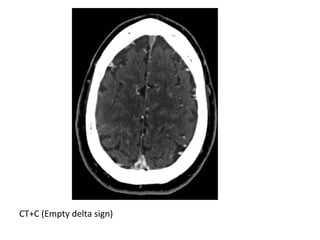

2-Empty Delta sign :

*The sign consists of a triangular area of enhancement

with a relatively low-attenuating center which is the

thrombosed sinus

*In early thrombosis the empty delta sign may be absent

and you will have to rely on non-visualization of the

thrombosed vein on the CECT

*The sign may be absent after two months due to

recanalization within the thrombus

CT+C : Empty delta sign due to thrombosis of the SSS

CTV (Empty delta sign)

CT+C (Empty delta sign)

CT+C ( Empty delta sign )